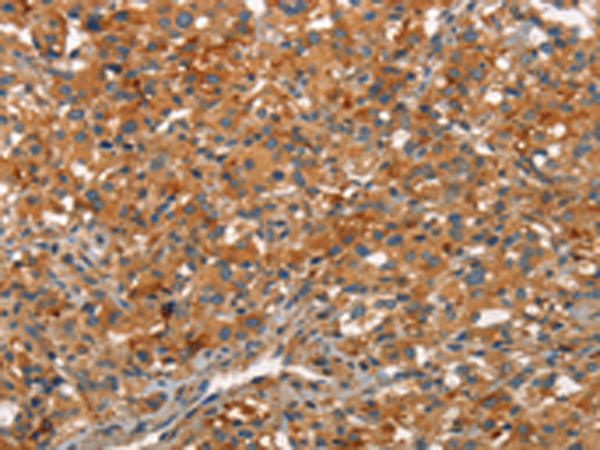

分类: 科研抗体货号: P11197别名: ARC34; PRO2446; p34-Arc; PNAS-139应用: WB,IHC反应种属: Human, Mouse, Rat